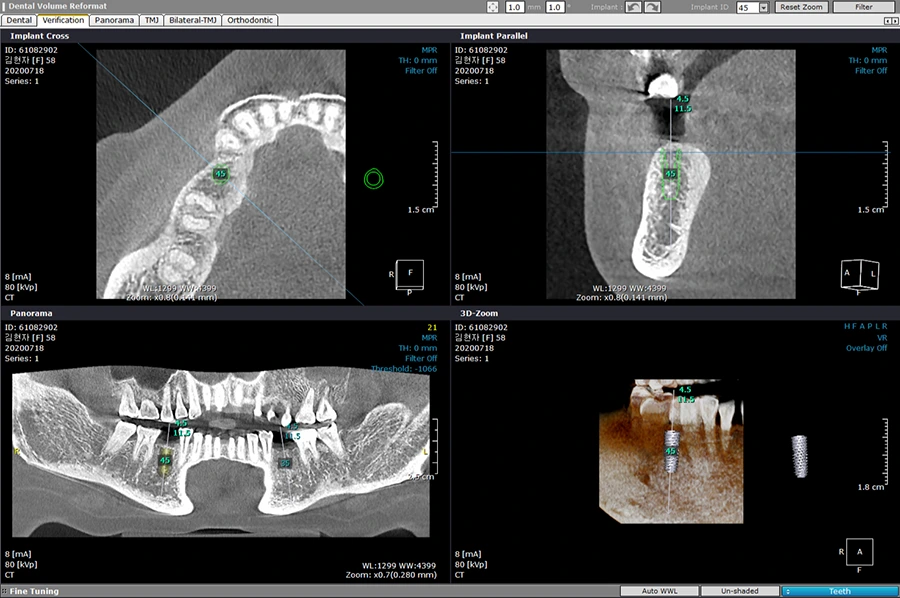

2. X-ray 또는 CT촬영

임플란트 치료 시 X-ray와 CT촬영을 합니다. 특히 CT촬영은 수술 부위의 골밀도 평가와 치조골의 상태를 정확하게 확인하기 위해 꼭 필요한데요.

CT를 이용하면 잇몸을 절개하지 않고도 환자의 구강구조를 정확히 알 수 있을 뿐 아니라 턱뼈의 구조와 치골의 폭과 길이까지도 정확하게 확인할 수 있기 때문에 인공치아뿌리를 심는데 필요한 절개를 최소한으로 할 수 있어 출혈과 상처가 아무는 기간을 줄일 수 있습니다. 이때 어떤 CT장비를 사용하는가에 따라 임플란트 비용이 차이가 날 수 있습니다. 저희 에스다인치과에서는 3D CT촬영 장비를 통해 임플란트 시술 전 상태를 파악하여 시술이 되어야 할 부위와 치아 배열까지 고려한 뒤 치료계획을 꼼꼼히 세워 치료를 진행하고 있습니다.